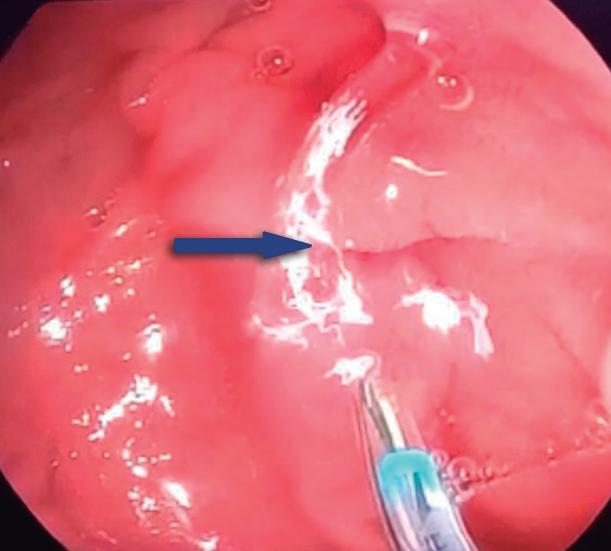

Páncreas Anular

Consiste en una anomalía de la migración del brote pancreático ventral, el cual no rota o lo hace de manera incompleta, resultando en la presencia de tejido glandular pancreático a la derecha del duodeno, rodeando a su 2° porción (Figura 8). Han sido descriptos dos subtipos: el extramural, donde el conducto de Wirsung rodea al duodeno uniéndose al conducto pancreático principal; y el intramural, donde el tejido pancreático se entremezcla con la pared duodenal y sus secreciones drenan directamente a la luz a través de conductos muy pequeños.16

En las imágenes encontramos parénquima pancreático rodeando a la 2° porción duodenal, habitualmente en toda su circunferencia y en ocasiones de manera incompleta. En la colangio-RM es posible visualizar al conducto pancreático a la derecha del duodeno, con un recorrido que se dirige a la ubicación de la papila mayor (Figura 9).17

A) Resonancia magnética secuencia T1 con gadolinio, plano axial. Las flechas señalan el parénquima del páncreas prolongado hacia la derecha “abrazando” a la 2° porción duodenal (cabeza de flecha). B) Resonancia magnética, secuencia T1 con gadolinio, plano axial, corte más caudal al previo. Las flechas nos muestran al páncreas rodeando de manera completa a la 2° porción del duodeno. C) Resonancia magnética, secuencia T2, plano coronal. La flecha señala presencia de parénquima glandular y conducto pancreático a la derecha del duodeno (cabezas de flecha). D) Resonancia magnética, secuencia T2, plano coronal, corte posterior al previo. El páncreas anular y su conducto de drenaje rodean en forma completa al duodeno (cabezas de flecha). E) Colangio-RM. El conducto del páncreas ventral (flechas) hace un giro, rodea al duodeno (cabeza de flecha) y se une al conducto pancreático principal para drenar en la papila mayor. F) Colangio-RM. La imagen magnificada muestra con mayor detalle el recorrido del conducto de Wirsung en el contexto de un páncreas anular.